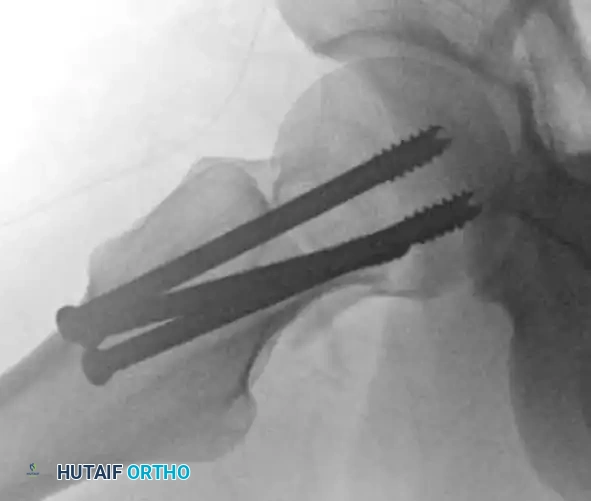

Figure: Anteroposterior radiograph demonstrating a severe varus malreduction of a femoral neck fracture following initial cannulated screw fixation.

Figure: Anteroposterior radiograph revealing an established nonunion of the femoral neck with hardware failure and backing out of the cannulated screws.